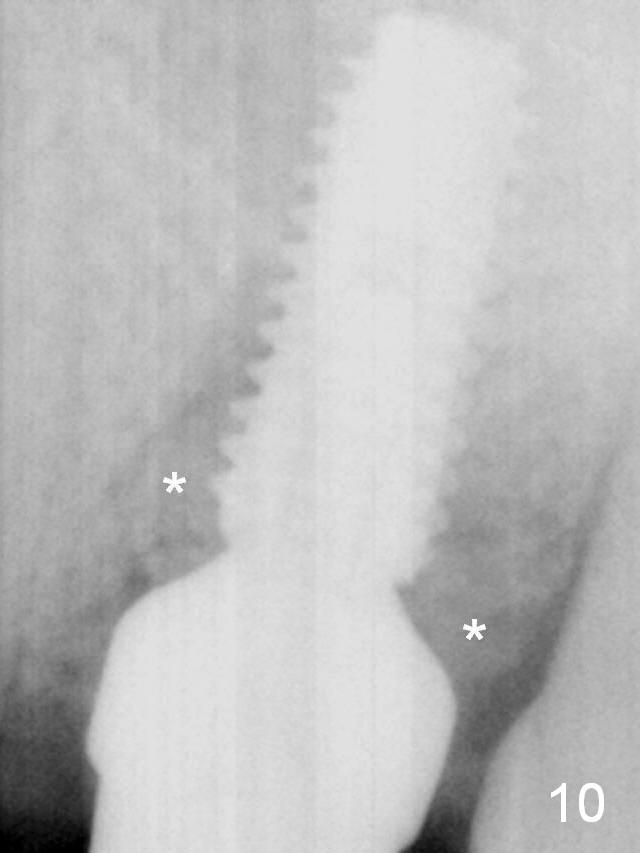

A 5x11.5 mm implant is placed with insertion torque of 35 Ncm with ~ 2 mm sticking into the sinus with bone graft and 1.5-2.5 mm outside the septum. The latter is covered by bone graft (Fig.10 *).